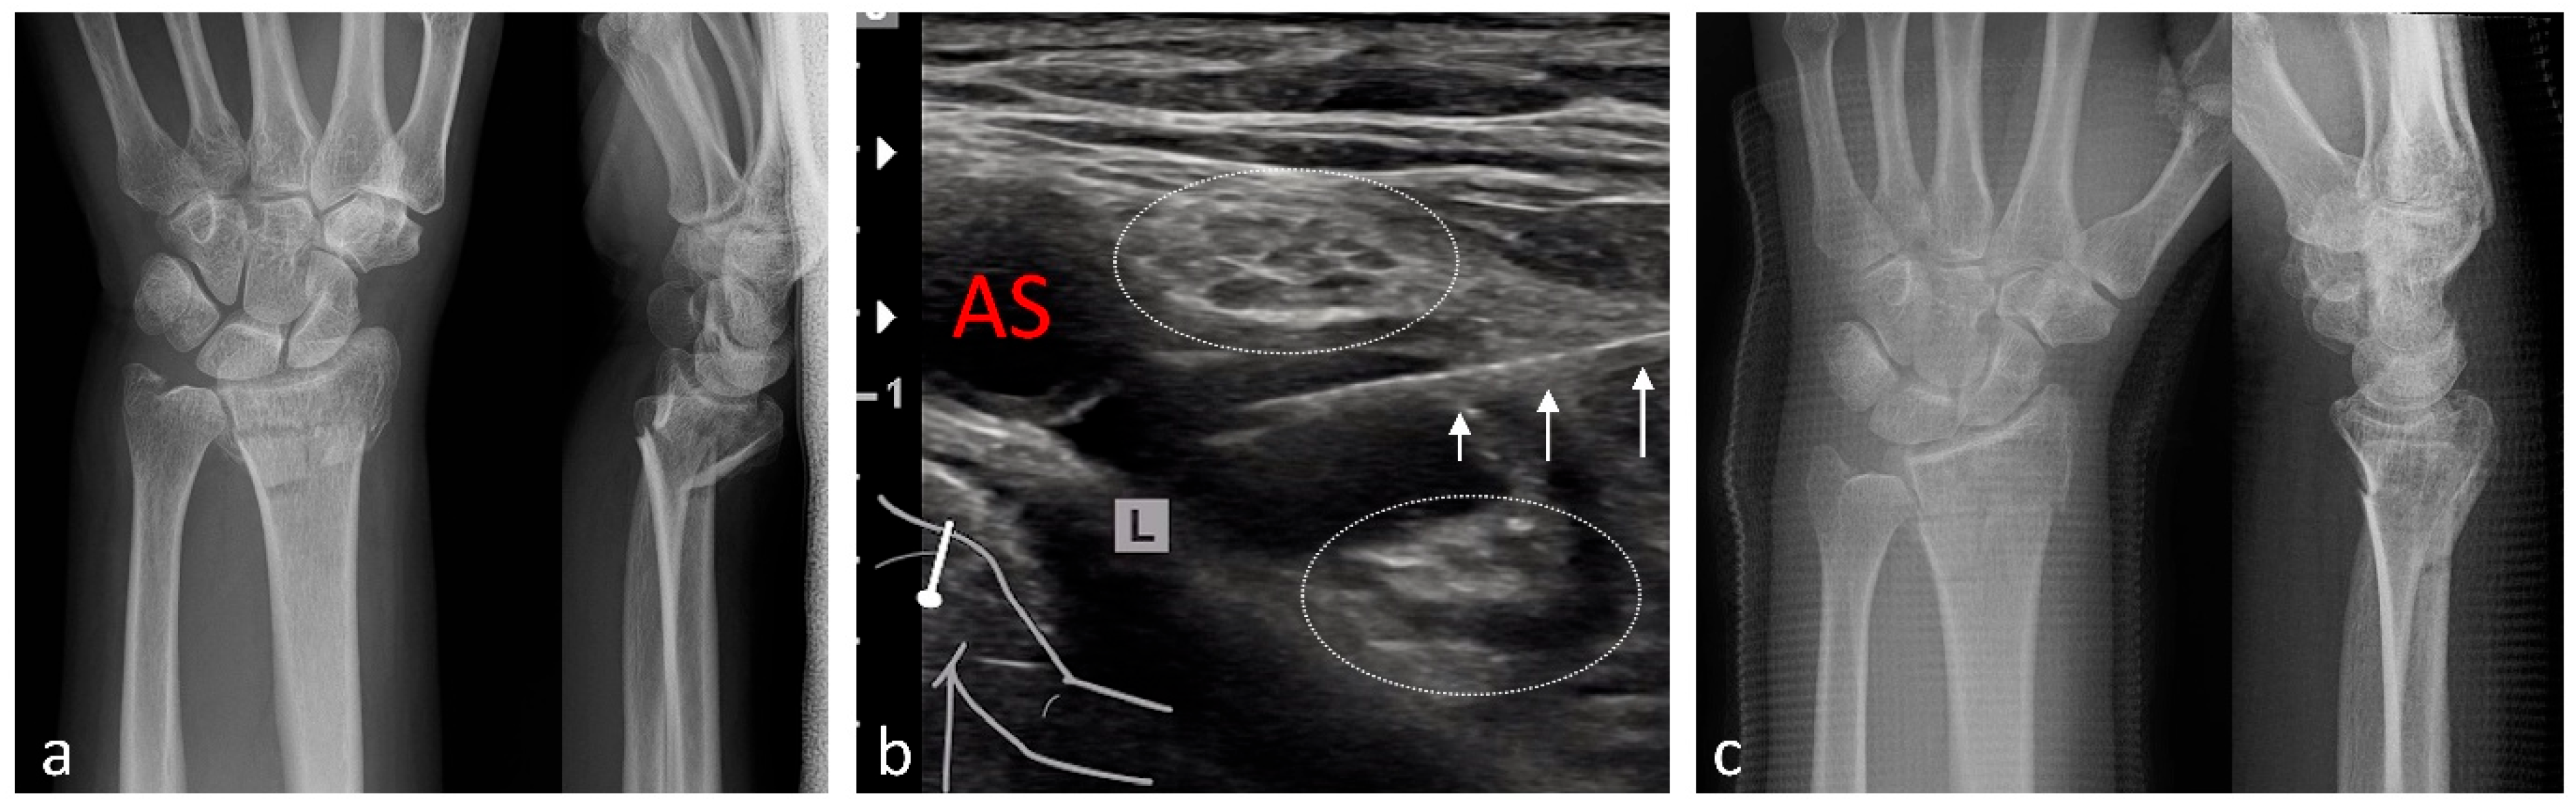

| Radius | 111 | Brachial plexus block (infraclavicular)/10–20 |

| Shoulder | 99 | Brachial plexus block (interscalene)/3–5 |

| Wrist | 1 | Brachial plexus block (infraclavicular)/15–20 |